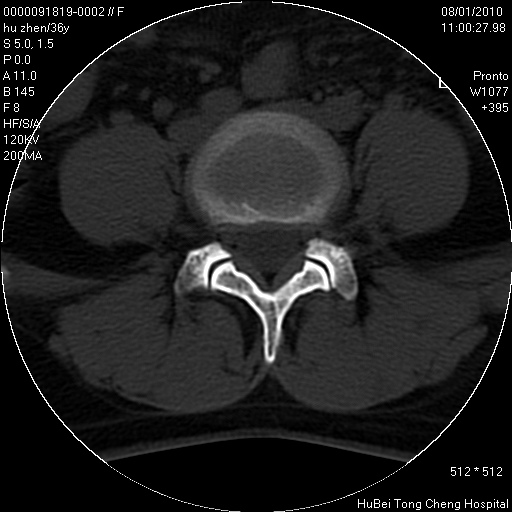

患者 女,36岁。右侧腰腿痛半月余。腰骶椎mr平扫偶然发现骶椎异常信号。

临床诊断:1)腰椎间盘突出症。2)骶椎肿瘤性病变?

骶椎ct平扫(层厚、层距均为5mm),图像如下: